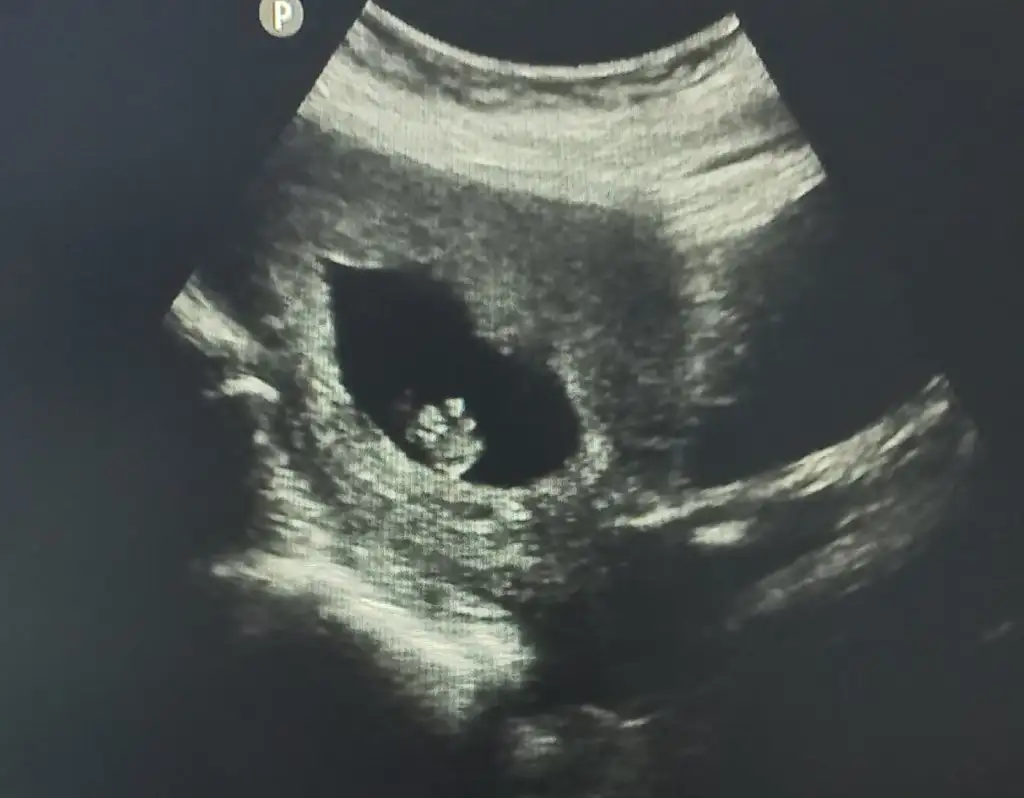

8+3 karindan kizlar yorum bekliyorum

Eklentiler

• 20230413_153445.webp

20230413_153445.webp

32,1 KB · Görüntüleme: 98

• 20230413_153449.webp

20230413_153449.webp

12,7 KB · Görüntüleme: 93